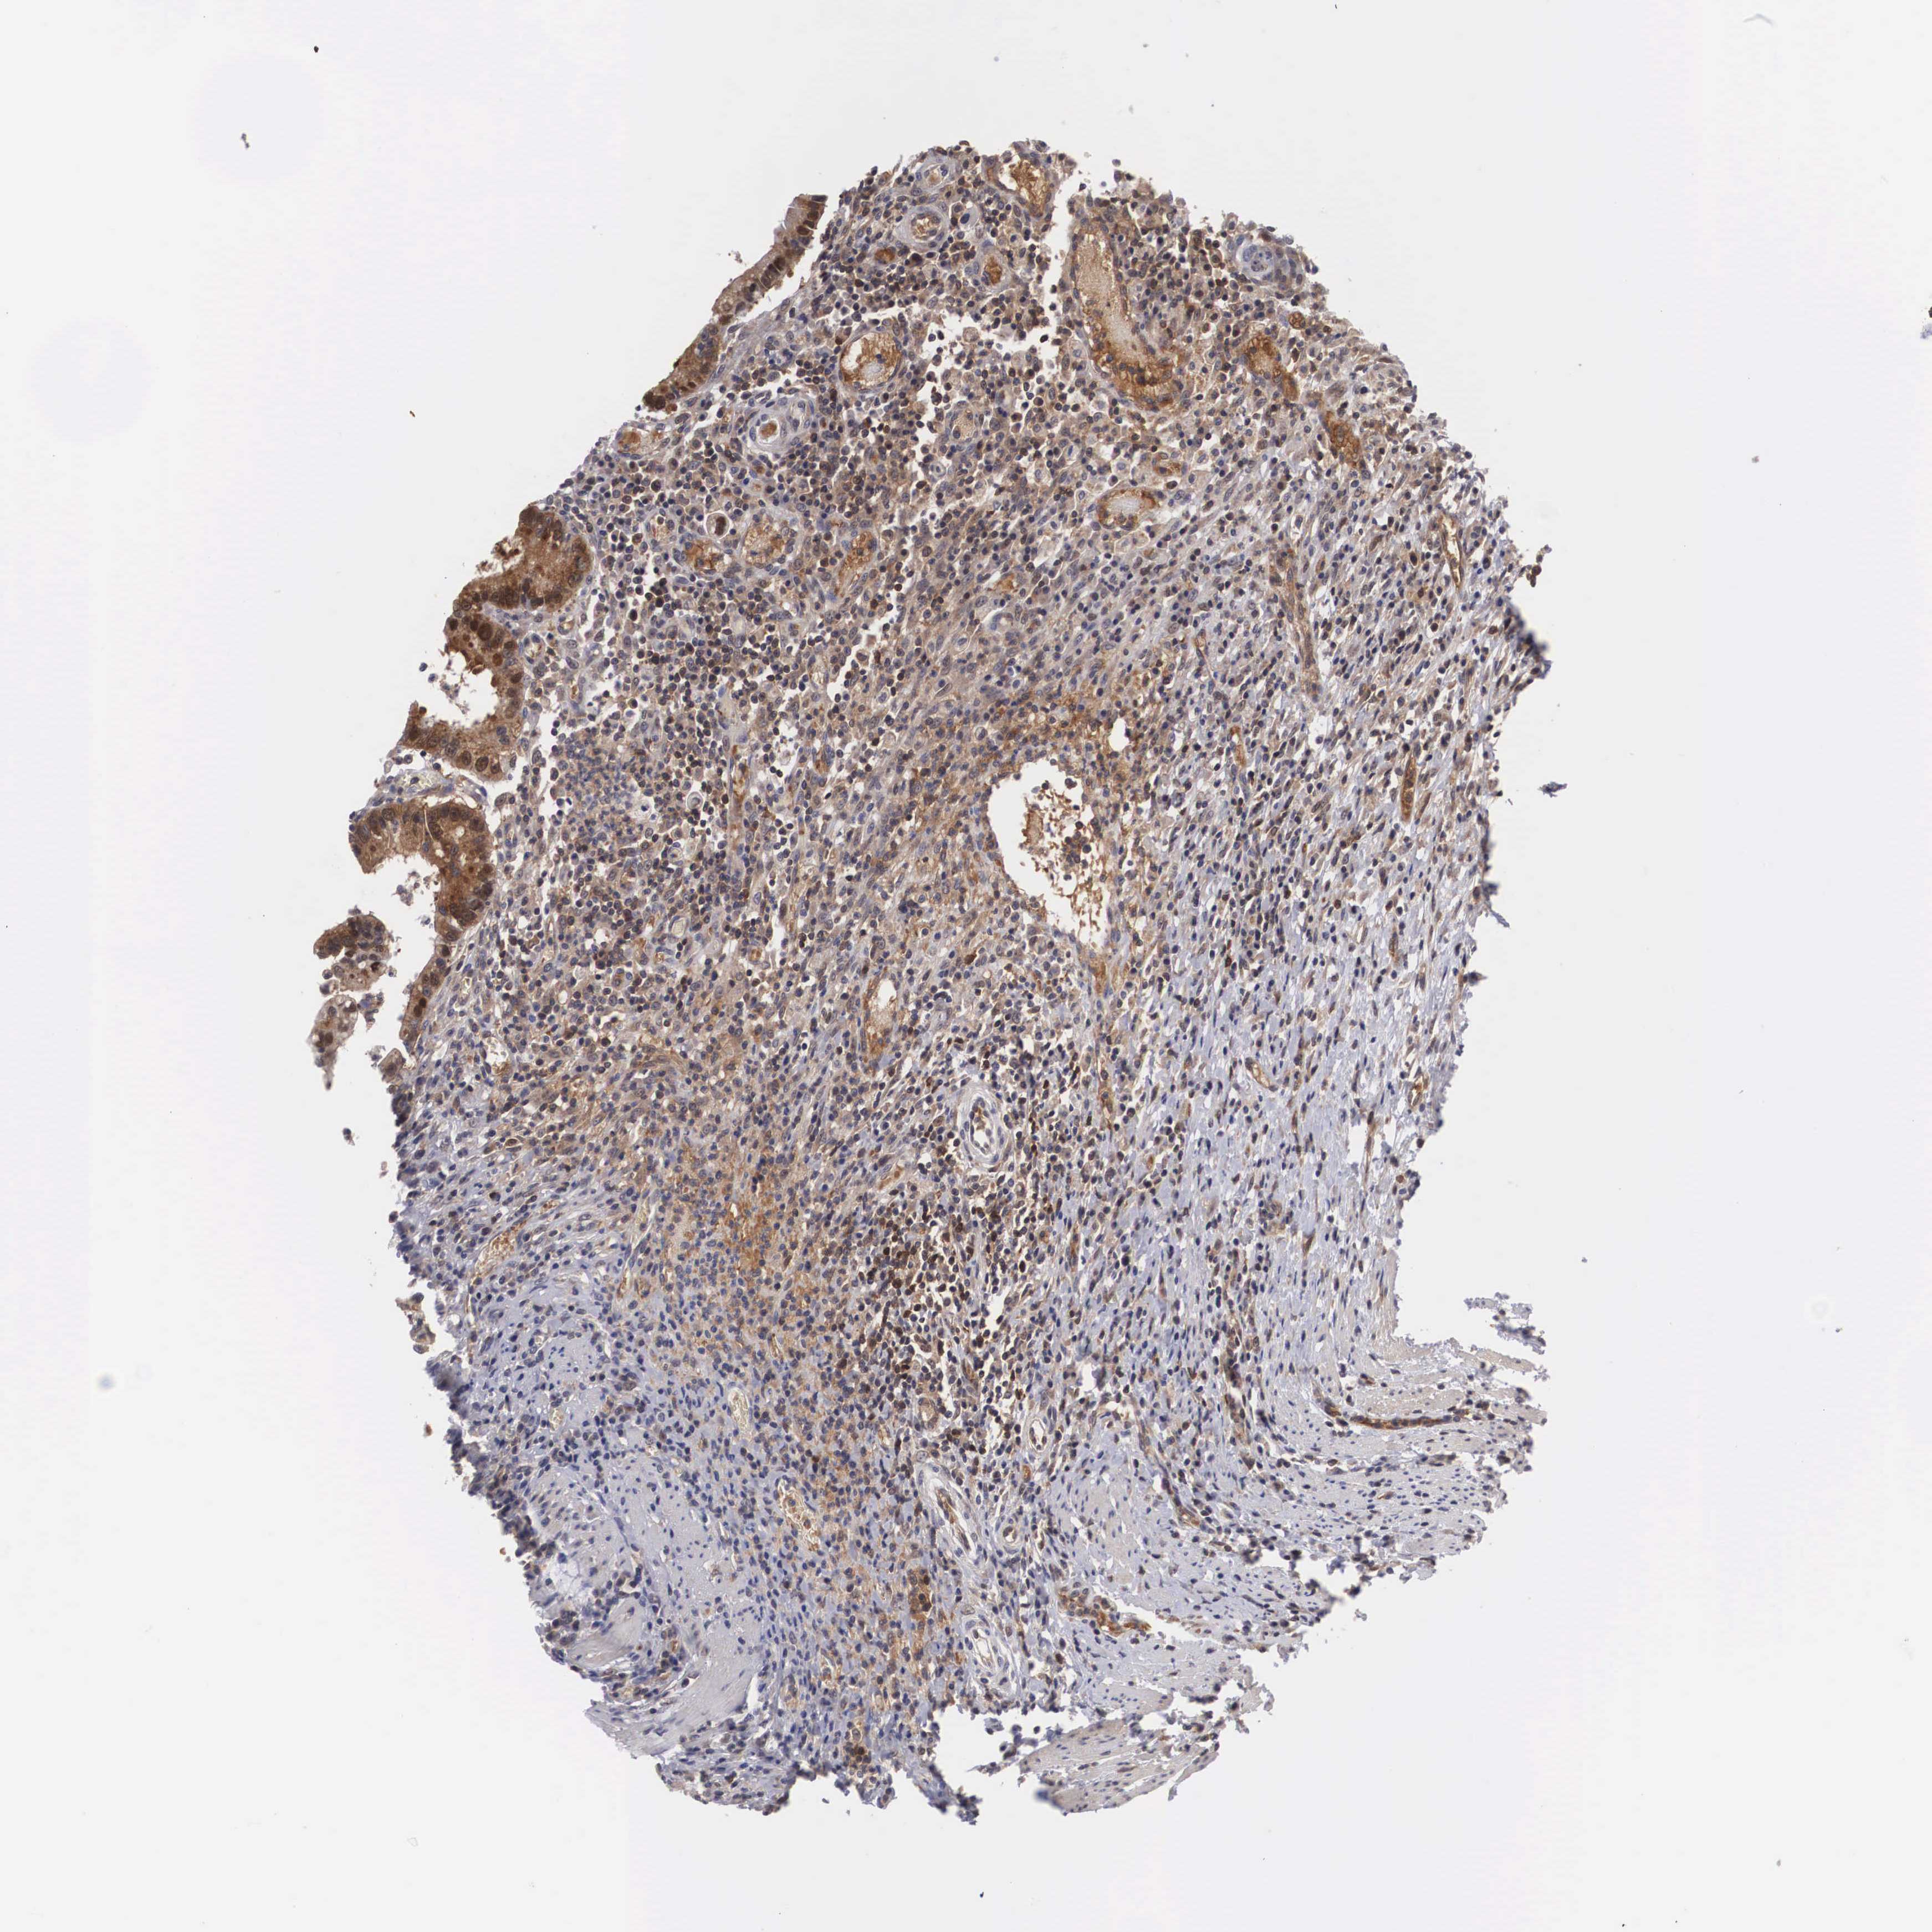

CANCER COLORECTAL CANCER Show tissue menu

ANTIBODIES

AND

VALIDATION